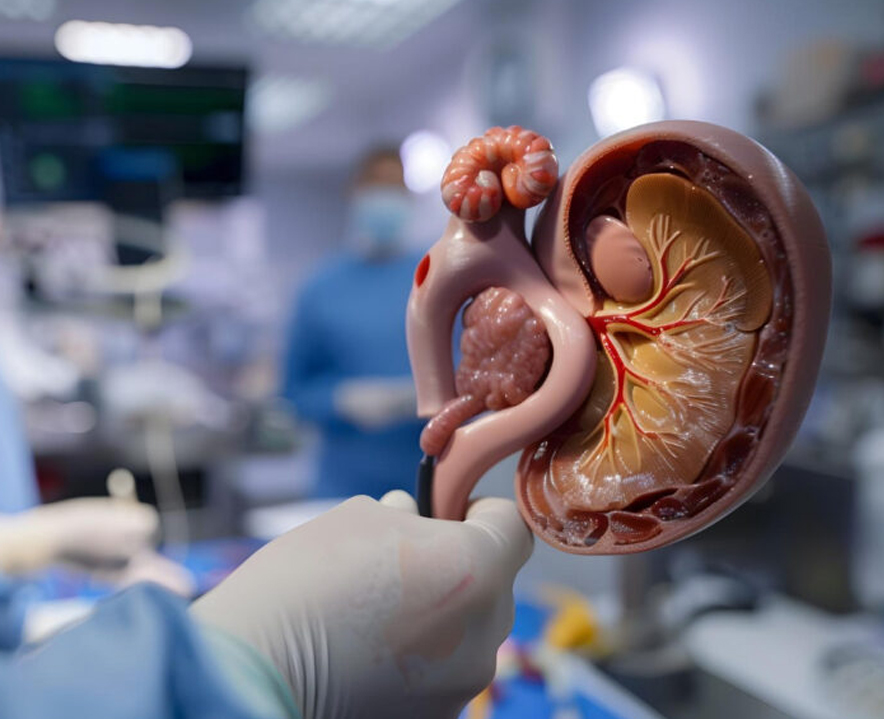

Kidney Transplant Evaluation & Renal Surgical Procedures

Complete pre-transplant assessment and advanced renal surgeries.